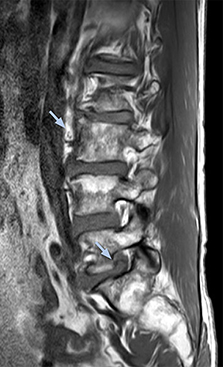

“For example, in sagittal images, when the presence of fat is observed in the intervertebral foramen, it suggests that there is a margin around the nerve. Similarly, the absence of fat indicates that the nerve is being compressed. So, we used to deduce nerve compression indirectly. With NerveVIEW, however, we can observe the condition of the nerves directly, regardless of the presence or absence of fat. We always prefer such direct observation of anatomy over having to make an inference about it.”

“Although symptoms of typical disc herniation and atypical hernia are very similar, the actual site of herniation is different. It is therefore important to characterize the nerve’s condition both inside and outside of the intervertebral foramina. “Conversely, if we see no abnormality in NerveVIEW, we can assume at least that there is no severe condition that requires surgery. Like this, it can help us avoid unnecessary surgery. NerveVIEW can have a tremendous impact in this way.”

“NerveVIEW is really useful for those cases where a nerve disorder is strongly suspected based on the clinical examination but our regular MRI images do not show any findings. These atypical herniations and spinal canal stenosis, occurring in 5% to 15% of the total lumbar herniation/stenosis cases are our main target when using NerveVIEW,” says Dr. Yabuki.

“The intra-luminal signal of veins, especially around the intervertebral space, can be suppressed well with NerveVIEW. As a result, we can easily observe the detailed nerve structure around the posterior ganglion,” he says. “This is why we use 3D NerveVIEW for intraforaminal stenosis and extraforaminal stenosis/herniation (lateral disc herniation). On the other hand, if herniation is suspected to exist inside the dorsal root ganglion (DRG), balanced TFE or ProSet-FFE is applied. NerveVIEW is not suitable for evaluating the median type of herniation.” The SE-EPI DWI-based method for MR neurography works well for large FOV exams like whole-body MRI, but focal examination of nerves is often limited by the attainable spatial resolution (both inplane and slice direction) and geometric distortion. “3D NerveVIEW achieves higher in-plane resolution – close to our other routine spine sequences – and the source images can be used instead of adding a fat-suppressed T2-weighted sequence,” Tanji says.

“Recently, the two surgical methods extreme and oblique lateral interbody fusion (XLIF and OLIF) have become mainstream for minimally invasive treatment of lumbar spinal canal stenosis and intervertebral foramen stenosis. With these surgical techniques, the spine is approached from the flank, and prior knowledge of the exact anatomy of the lumbosacral plexus would be extremely helpful. To that end, high slice resolution (less than 1 mm acquisition) that enables sharper sagittal MPR images will be needed.”